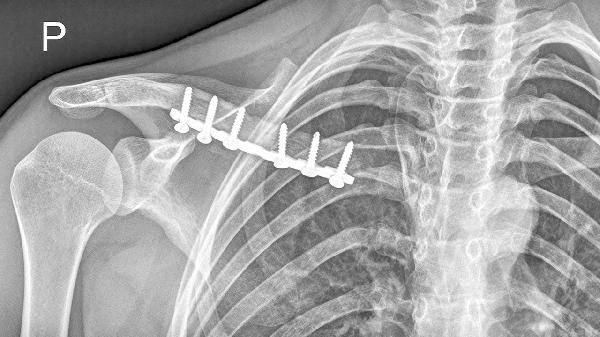

5、就医检查

持续超过2周的疼痛需进行胸部X光、CT或心电图检查。突发剧烈疼痛伴随呼吸困难可能提示气胸,需急诊处理。长期吸烟者出现该部位隐痛应排查肺尖部肿瘤。女性患者还需鉴别乳腺疾病放射痛,必要时进行乳腺超声或钼靶检查。